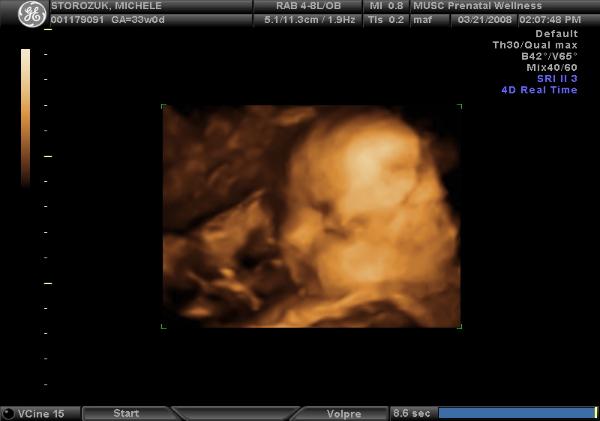

Clayton Luke Storozuk

Clayton